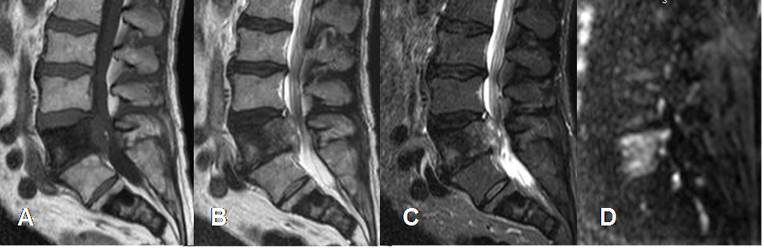

Fig 223. Fracturas por osteoporosis.

A: RM sagital en T1, B: RM sagital en STIR y C: RM sagital en difusión.

Pérdida de altura en varios cuerpos vertebrales dorsolumbares. En T1 conservan su señal y sus bordes son angulados, lo que sugiere etiología benigna. (Flechas delgadas). La vértebra D11 es algo hiperintensa en la parte anterior, indicando evolución aguda. (Flecha gruesa). Todos los cuerpos son hipointensos en la difusión, por fracturas de origen osteoporótico.